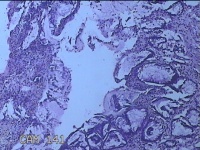

性别

男

年龄

40岁

临床诊断

混合痔

一般病史

反复肛门肿物突出15年。

标本名称

肛门肿物

大体所见

灰白暗红色肿物0.7x0.5x0.2cm一个,表面糜烂。

图1

脱水、透明,浸蜡、脱蜡效果不佳,制片质量差。